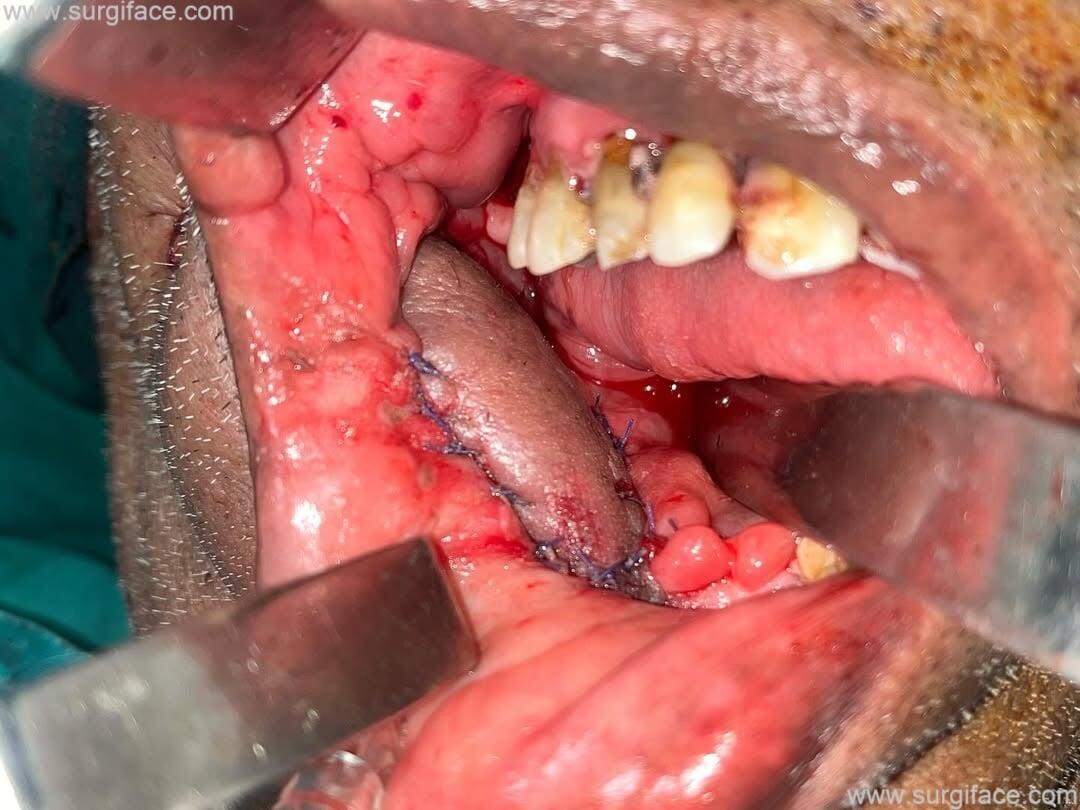

A case of Recurrent Verrucous Carcinoma Gingivobuccal Sulcus. Wide local excision performed, followed by reconstruction using a nasolabial flap.